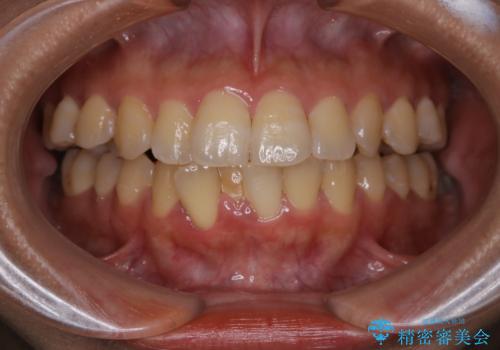

[マウスピース矯正] がたがたの歯並びをきれいにしたい

![[マウスピース矯正] がたがたの歯並びをきれいにしたいの症例 治療前](https://seimitsushinbi.jp/wp/wp-content/uploads/2025/06/0d238550c8a0fddc4de7b2c337c6c786-500x350.jpg?v=1750323380)

![[マウスピース矯正] がたがたの歯並びをきれいにしたいの症例 治療後](https://seimitsushinbi.jp/wp/wp-content/uploads/2025/06/IMG_0002-2-500x350.jpg?v=1750323305)